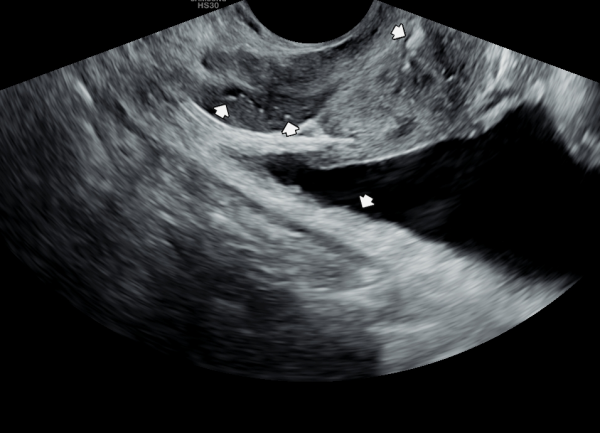

첫 내원 당일 정면 경직장 전립선 초음파 사진상 좌우 사정관 입구에 결설이 관찰되고 전립선의 결절이 관찰되는 초음파 사진입니다.

This is a frontal transrectal prostate ultrasound image taken on the patient's first visit, showing calculi (stones) at the openings of both ejaculatory ducts and nodules within the prostate.![]()

내원 첫날 정면 경직장 전립선 초음파 사진상 사정관 입구가 순환장애로 사정관의 낭종과 부분적 전립선 낭종들이 관찰되는 초음파 사진입니다.